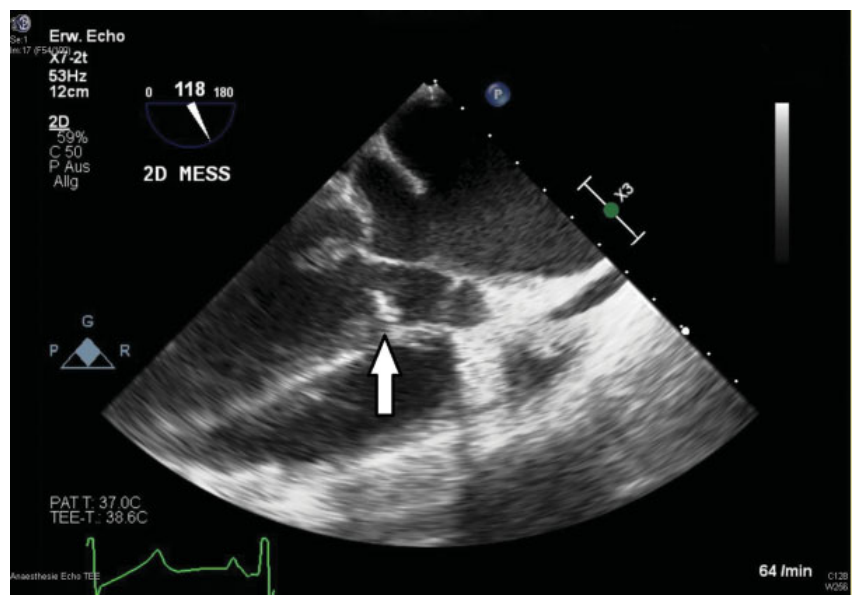

2012 年,检测到伴有轻度狭窄的二尖瓣圆顶。2018 年针对二尖瓣狭窄的择期球囊瓣膜成形术未成功(瓣孔面积为1.3cm2,峰压梯度为24mmHg,平均压力梯度为14mmHg)。患者因瓣膜置换术和左心室流出道梗阻入院 (峰压梯度为35mmHG,平均压力梯度为19mmHg)(图 1)。

图1. 左心室流出道瓣膜下膜(用箭头标记)的术中经食管超声心动图,尺寸为 1.0x0.5 厘米,可能与二尖瓣前叶相连。

在2008年心脏移植期间进行开胸手术后,在利用内窥镜并经右股骨插管进行体外循环的条件下,我们进行了右侧微创开胸手术。经食管超声心动图证实左心室流出道中有瓣下膜,尺寸为1.0x0.5 cm,可能与二尖瓣前叶相连(图 1)。左心室流出道中的侵入性峰压梯度为 25mmHg。